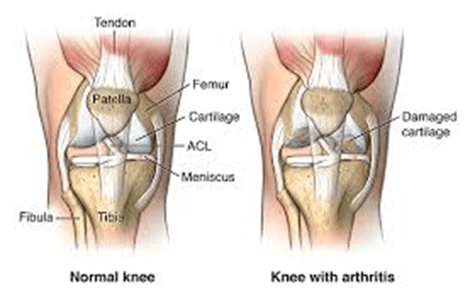

Arthroplasty is performed on people suffering from severe pain and disabling joint stiffness. Osteoarthritis (OA), a degenerative joint disease, is the most common condition causing joint destruction with pain and impaired movement. Other causes include rheumatoid arthritis (RA), hemophilia, synovitis, and rare bone diseases, which are all known to destroy cartilage. Joint resection, rather than joint replacement, is more likely to be performed on people with rheumatoid arthritis, especially when the elbow joint is involved. Joint replacement is usually reserved for older patients, because of the limited longevity of benefits. The younger the patient, the greater the reliance on medical treatment.

It is a method by which the surgeon removes the damaged cartilage and bone and replaces it with new metal and plastic joint surface to repair the connection and painless functioning of joints.

Various conditions can produce joint pain and disability and direct patients to consider joint replacement surgery. In many cases, joint pain is produced either from arthritis, a fracture, or another condition.